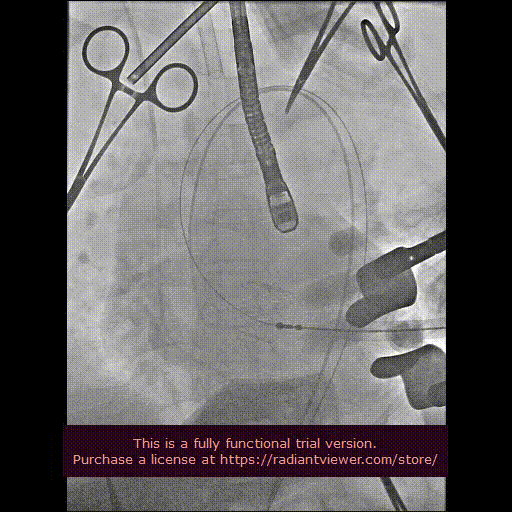

用经胸超声心动图确定心尖位置,并做好标记。常规肝素化,按照心尖标记,行第5、6 肋间左胸前外侧小切口,充分暴露心尖后将心包切开并悬吊,用3-0 Prolene 线加毛毡片完成荷包缝合。经股动脉植入6Fr鞘管,并插入猪尾造影导管至主动脉根部,造影确定主动脉瓣瓣环水平及两侧冠状动脉开口。

经心尖途径置入 J-Valve 瓣膜输送系统,在升主动脉部打开定位件,调整角度,轻轻向后牵拉输送器使定位件进入主动脉窦内。联合主动脉根部造影和食管超声观看定位件是否定位于窦底,形态随着心脏跳动而自然摆动即可。下降瓣膜至主动脉瓣环内,在主动脉瓣口释放瓣膜支架,此过程无需快速起搏。瓣膜成功释放后移除瓣膜输送系统。行主动脉根部造影及经食管超声检查,对瓣膜功能、位置情况进行术后即刻评估。确认位置良好、功能正常后,移除导丝及输送系统,并收紧心尖荷包缝线打结固定。

造影显示主动脉窦部

从心尖置入输送系统

定位件入窦

瓣膜降至瓣环平面

释放瓣膜

造影确认瓣膜位置

撤出输送系统

造影确认植入效果